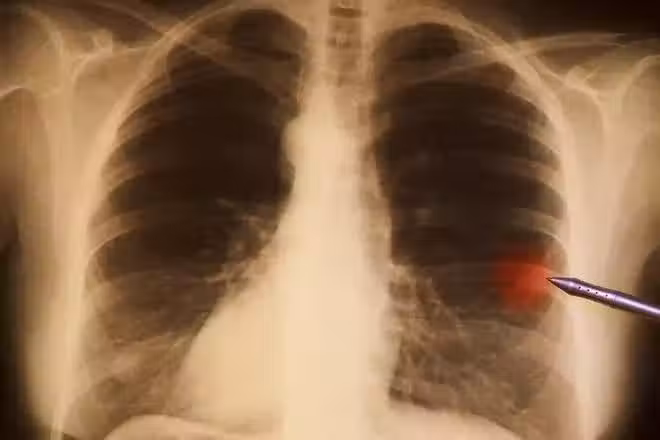

然而癌症卻還是盯上了他 ,2007年,寫完《中國新革命》,他 突然 暈倒 ,妻子陪著去做檢查,結果發現是肺癌晚期,全身多處有陰影,癌細胞已經向各處擴散,醫生說 要做好思想準備,可能活不過三個月。